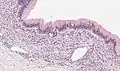

Microscopy

Mucinous cystadenoma of the pancreas